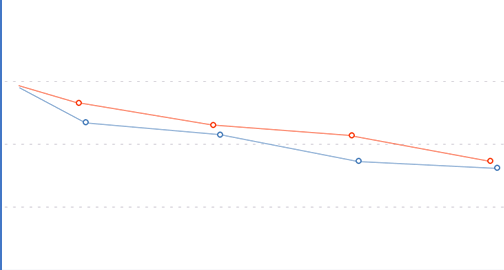

Die biologisch aktive Formel für Gelenke hilft, Operationen zu vermeiden und trägt zu einer effektiven Rehabilitation zu Hause bei.

Die Zusammensetzung von Hondro Sol ermöglicht es, die Dosis von NSAIDs zu reduzieren, die allmählich die inneren Organe zerstören. Hondro Sol ist wirksam und sicher bei längerer Einnahme.

Hondro Sol verursacht keine Nebenwirkungen, so dass es für Menschen mit Herz-Kreislauf-Erkrankungen und Magengeschwüren eingenommen werden kann.